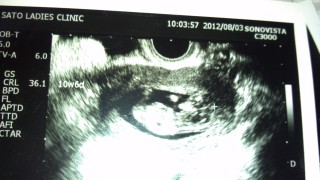

あまりに動いていたので、『普通はこんなんですか? 』と聞いたところ、先生『普通はもっとおとなしいですよ。すごい元気だね。』と大きさは3.6mmでした。